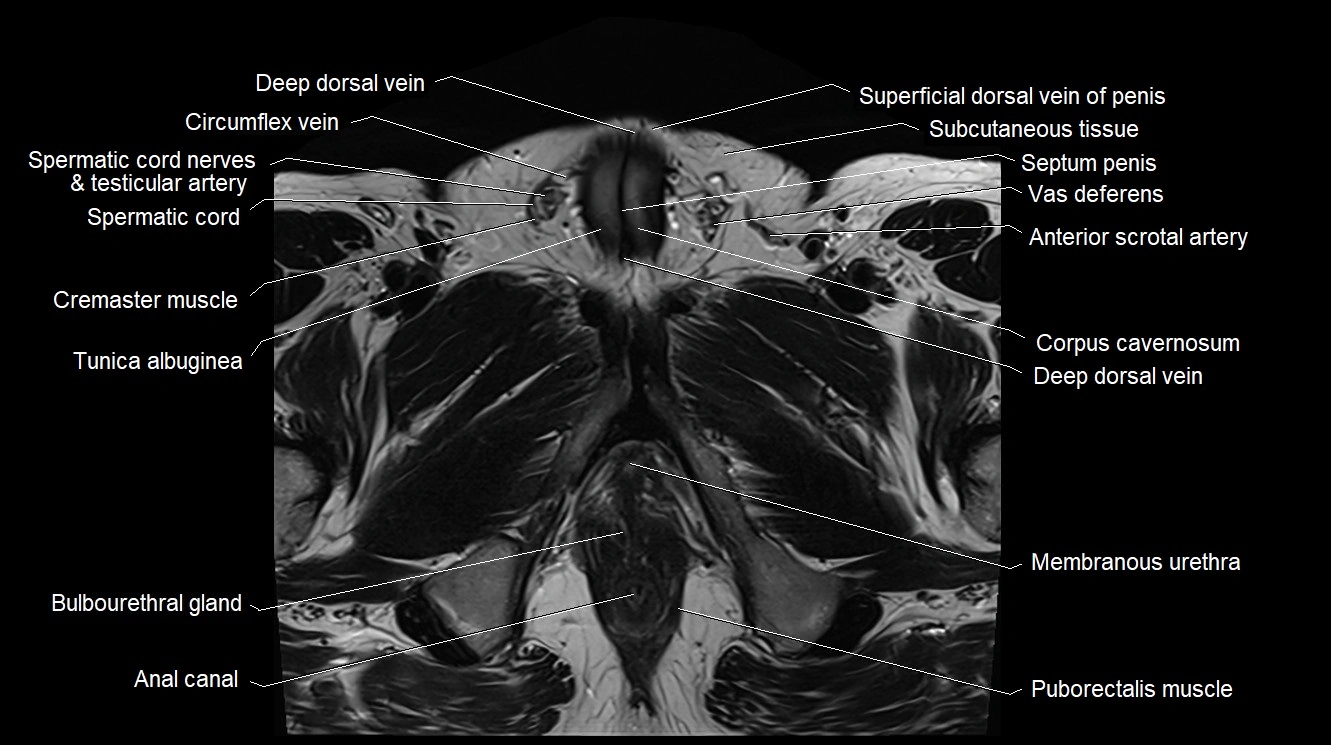

- Anal canal

- Bulbourethral gland (Cowper’s glands)

- Corpus cavernosum

- Cremaster muscle

- Deep dorsal vein of penis

- Membranous urethra

- Puborectalis muscle

- Septum of scrotum

- Septum of the penis (Penile septum)

- Spermatic cord

- Spermatic cord nerves

- Superficial dorsal vein of penis

- Testicular artery

- Tunica albuginea (penis)

- Vas deferens